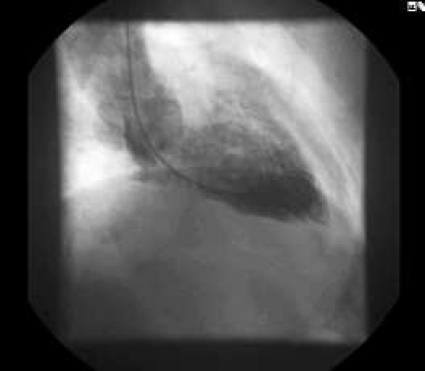

Fall 1 rör en 78-årig man, rökare med avancerad kroniskt obstruktiv lungsjukdom, som med hjälp av hemtjänsten inkom på grund av tilltagande andfåddhet. Vid ankomsten noterades en syrgassaturation på 67 procent. Patienten förbättrades efter inhalationsbehandling och steroider. EKG visade påtagliga ST-höjningar (Figur 2) och bedömdes som pågående akut hjärtinfarkt trots avsaknad av centrala bröstsmärtor. Akut koronarangiografi visade väsentligen normala kranskärl. Angiografi av vänster kammare visade dock betydande nedsättning av vänsterkammarfunktionen med akinesi/dyskinesi antero- och inferoapikalt samt hyperkinesi inom basala segment (Figur 3 A–B). Därutöver sågs ett betydande läckage i mitralisklaffen.

Efter undersökningen var patienten relativt välmående. Man fortsatte med andningsvård, inhalationer och startade behandling med ACE-hämmare i låg dos. Plasmavärdet av troponin I nådde som mest 3,0 (my)g/l (referensvärde 0,1 (my)g/l), medan CK-MB nådde 22 mg/l (referensvärde 4,0 (my)g/l). Dag 2 förflyttades patienten till hemortslasarettet och kunde så småningom skrivas ut.

Angiografisk kontroll ca 3 månader senare visade normaliserad vänsterkammarfunktion (Figur 3 C–D) med regress av både den apikala dyskinesin och mitralklaffläckaget. EKG i samband med kontrollangiografin visade regress av ST-höjningarna, normalisering av R-vågsprogressionen och tillkomst av T-vågsinversion (Figur 2).